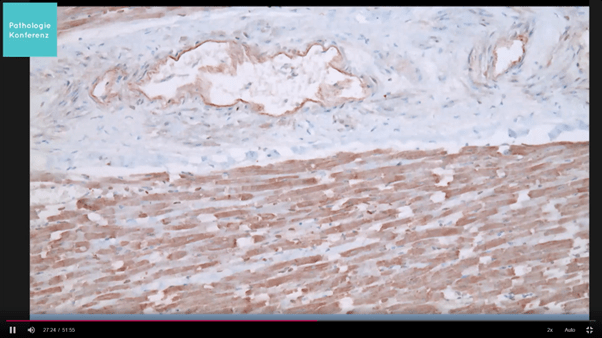

Vaccine Injuries: Pathology Images

The following are a few images (some potentially disturbing) of what pathologists are seeing worldwide. It is not at all clear what NZ pathologists are looking for when they examine a person who has died following Covid-19 vaccination. It is not clear how many post-mortems have been done. We do not know if they are staining tissues for the presence of spike protein, or whether they are looking for vascular inflammation or micro clotting.

The images below are from Prof Arne Burkhardt Pathology Conference 11 Mar 2022 Germany unless otherwise referenced.